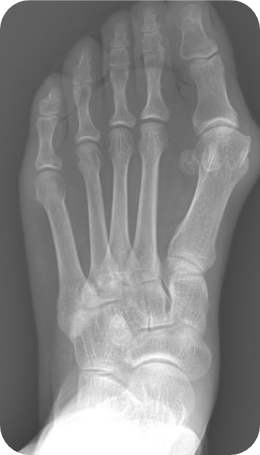

▲ 무지외반증 교정술 전